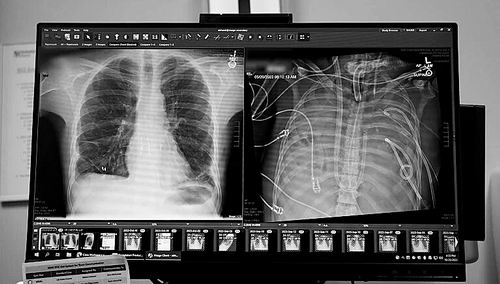

X光片显示的一名33岁患者的新肺(左)和旧肺。图片来源:美国西北大学

本报讯 一名33岁的男子在没有肺的情况下存活了48小时。一个医疗团队用一套体外人工肺系统维持了这名男子的生命,直到他接受了双肺移植手术。1月30日,相关研究结果发表于《医学》。